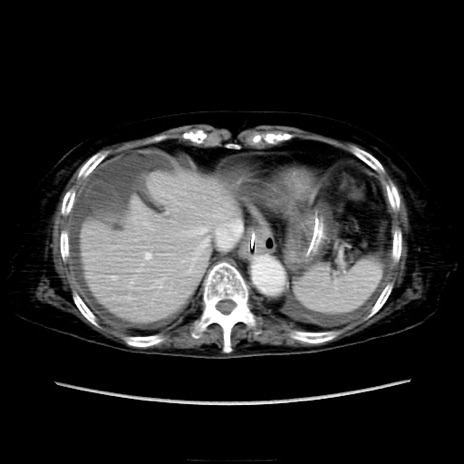

他院CT

横断像

冠状断像

矢状断像